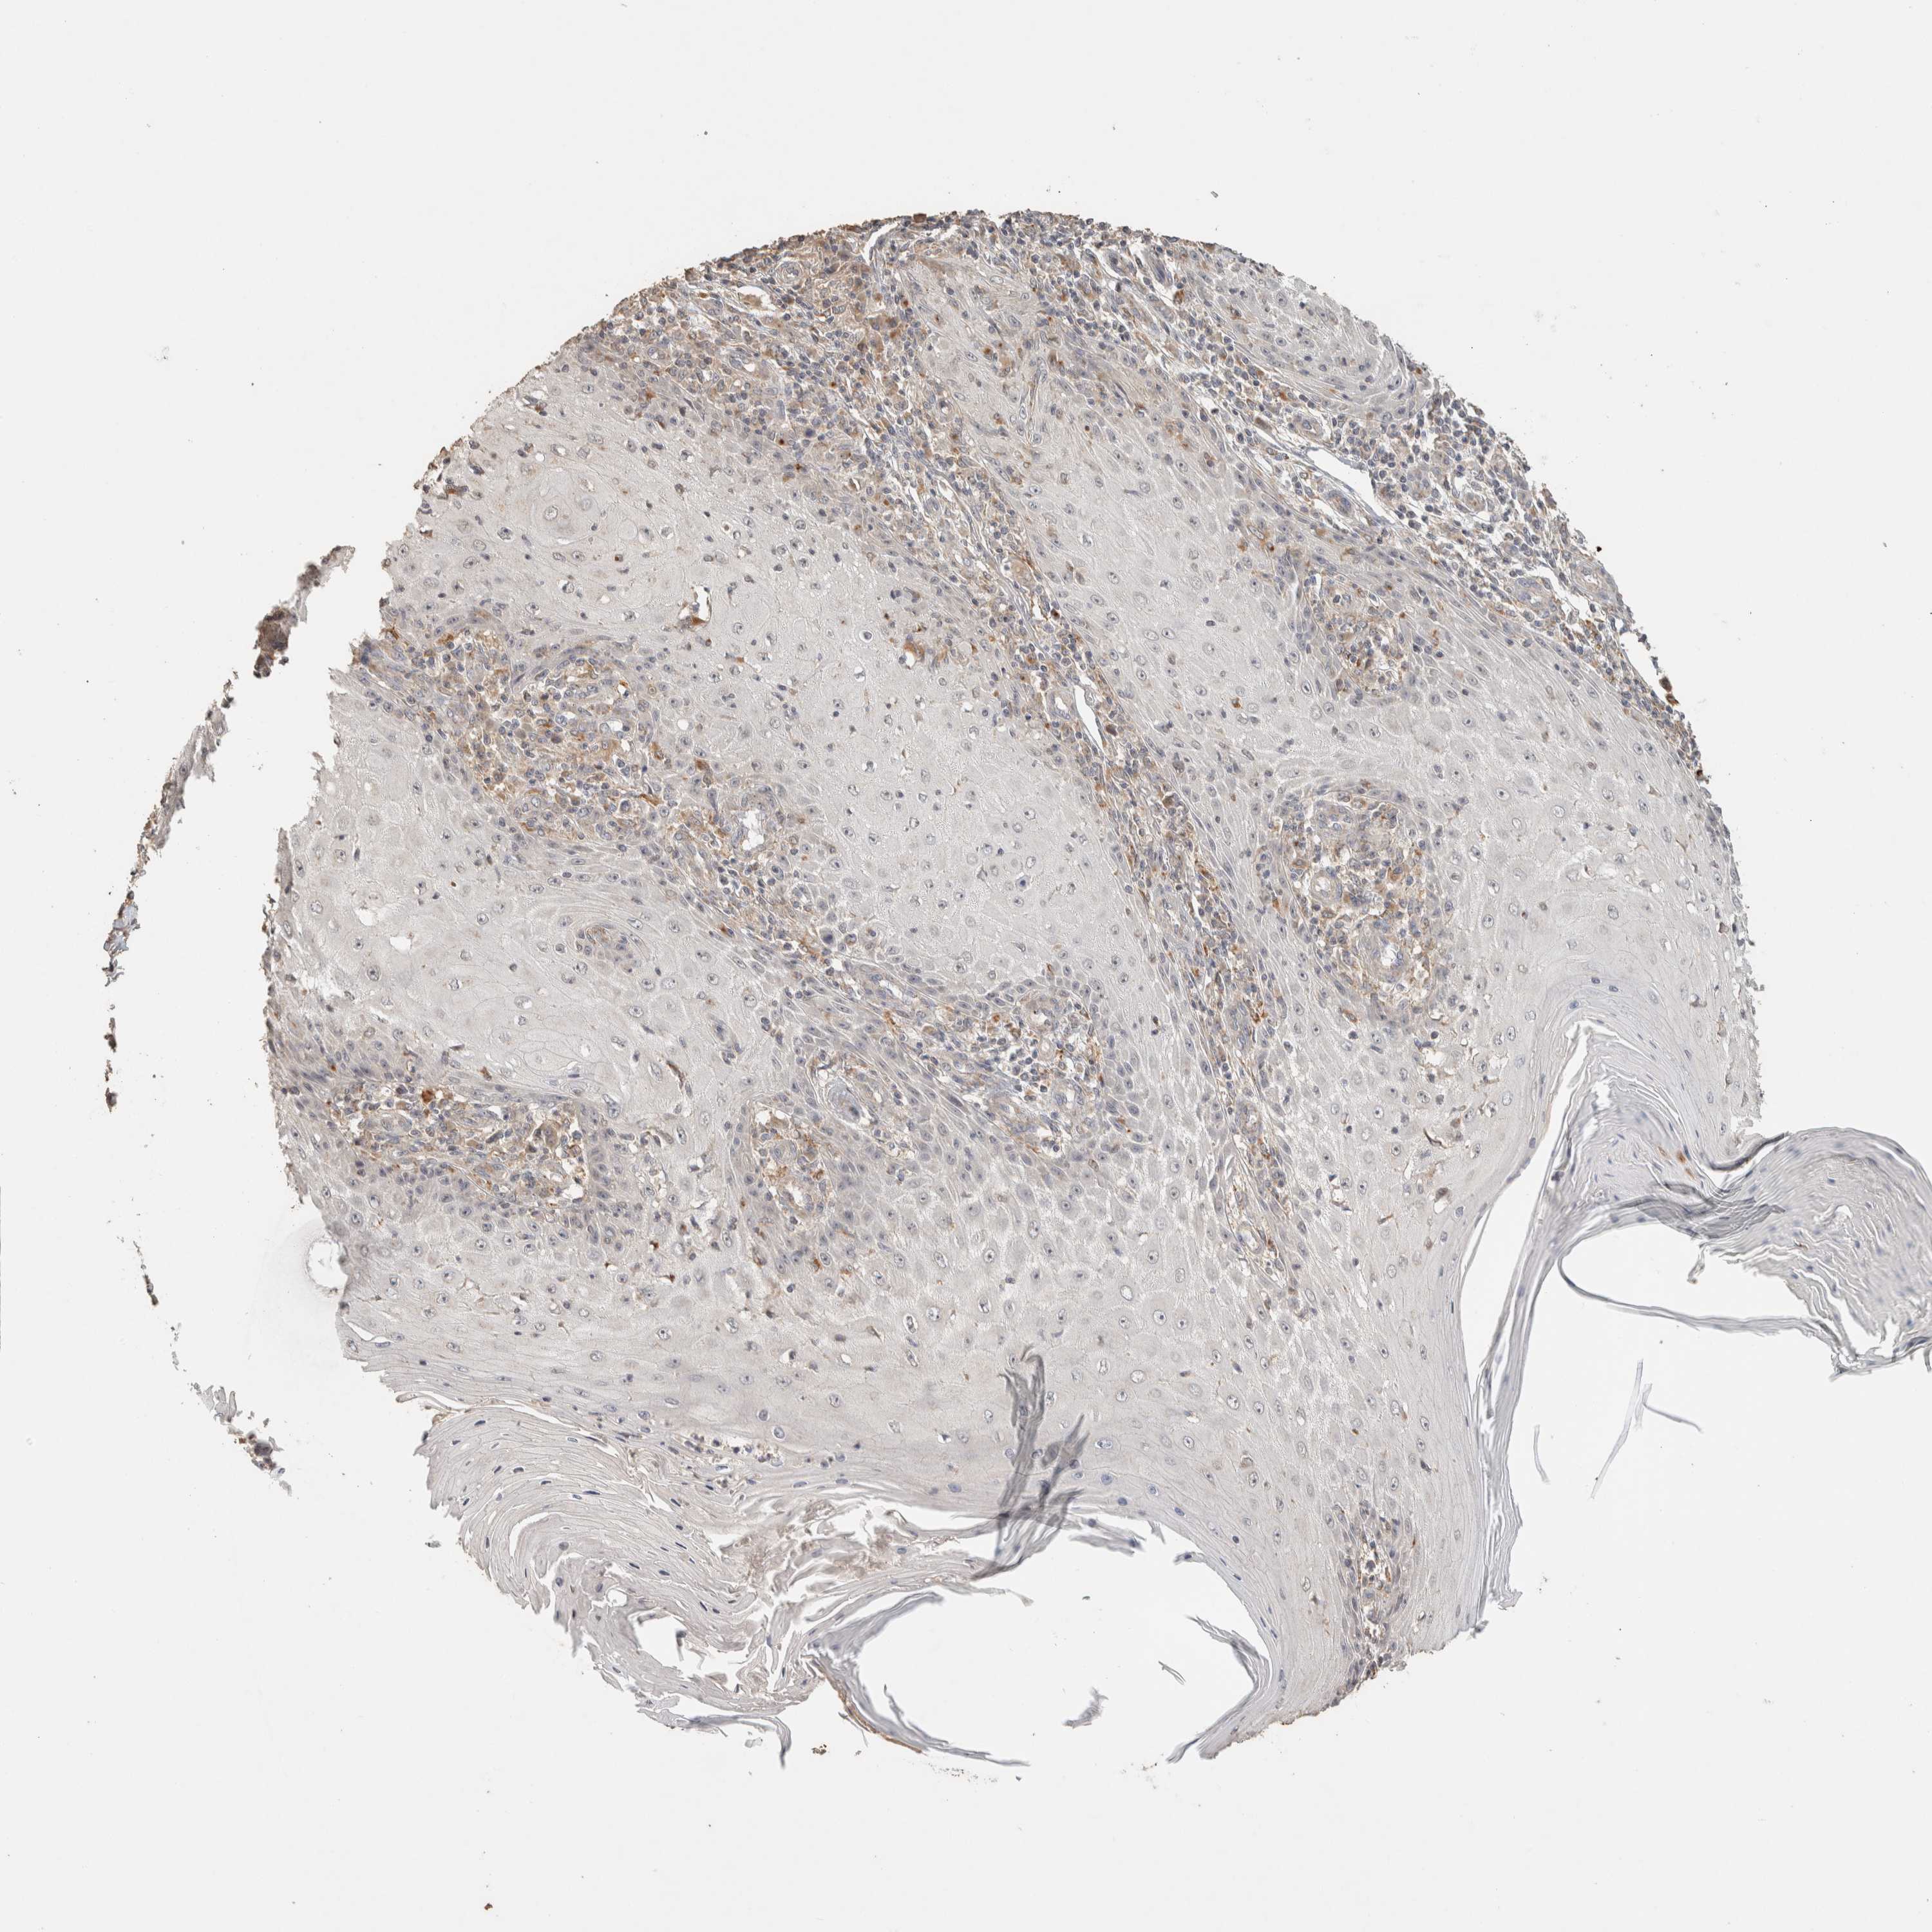

SKIN CANCER - Protein expressioni

A mouse-over function shows sample information and annotation data. Click on an image to view it in a full screen mode. Samples can be filtered based on level of antibody staining by selecting one or several of the following categories: high, medium, low and not detected. The assay and annotation is described here.

Antibody stainingi

Antibody staining in the annotated cell types in the current human tissue is reported as not detected, low, medium, or high, based on conventional immunohistochemistry profiling in selected tissues. This score is based on the combination of the staining intensity and fraction of stained cells.

Each image is clickable and will lead to virtual microscopy that enables deeper exploration of all samples and also displays staining intensity scores, fraction scores and subcellular localization as well as patient and tissue information for each sample.

Antibody HPA022824

Staining

High

Medium

Low

Not detected

Intensity

Strong

Moderate

Weak

Negative

Quantity

>75%

75%-25%

<25%

None

Location

Nuclear

Cytoplasmic/membranous

Cytoplasmic/membranous,nuclear

Basal cell carcinoma